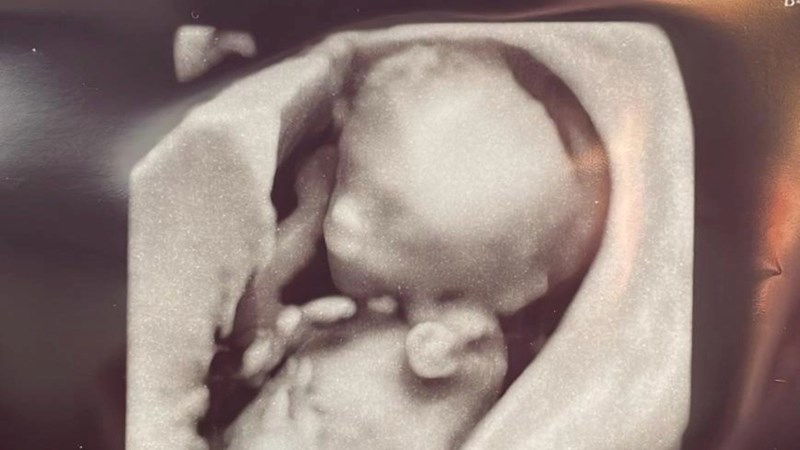

Me and my partner Faith have been on a journey we never expected. Towards the end of 2024, we discovered we were pregnant and couldn't have been more excited. At 15 weeks, we went for an early gender scan, and while we were thrilled to hear we were expecting a boy, the news soon took a heartbreaking turn.

The sonographer informed us that our son had lost his left hand, and we rushed to Darlington Hospital for another scan which confirmed the news, we were then rerffered to the RVI for more scans and tests. After a consultation at RVI, we learned that our son was affected by Amniotic Band Syndrome (ABS)—a rare condition where fibrous bands in the amniotic sac can wrap around body parts and cause deformities. Unfortunately, the band had severed his left hand from the mid-forearm. The good news is that at this stage, he would not have felt any pain, as his pain receptors weren’t developed yet.

As you can imagine, the emotional toll on Faith and me has been overwhelming. The constant worry of “Is he safe?” and “What else might the band affect?” has been ever-present. Now, at 31 weeks, unfortunately the band remains and more have formed but our little warrior is growing healthy. However, we continue to attend weekly scans, and the doctors have informed us that due to this an early delivery is expected.